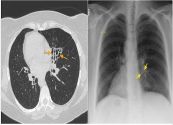

Bệnh lao kê là một dạng bệnh lao đặc trưng bởi các tổn thương nhỏ với kích thước 1–5 mm lan khắp cơ thể. Bệnh lao kê có thể lây nhiễm bất kỳ cơ quan nào như phổi, gan và lá lách. Vậy nguyên nhân và triệu chứng của bệnh là gì? Làm cách nào để chữa trị bệnh hiệu quả? Tham khảo ngay bài viết dưới đây để hiểu rõ hơn nhé!